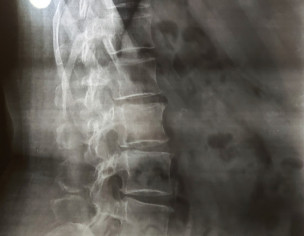

I have pain in my tail bone. Now I have when I sit or stand or lay on bed. Doc said its inflammation HISTORY--> tailbone was injured by falling 2 times at the same spot 5 years ago. I had that similar pain always while sitting or standing for long time but now it has increased n its very painful cant sit in my class. XRAY ATTACHED Thank you in advance